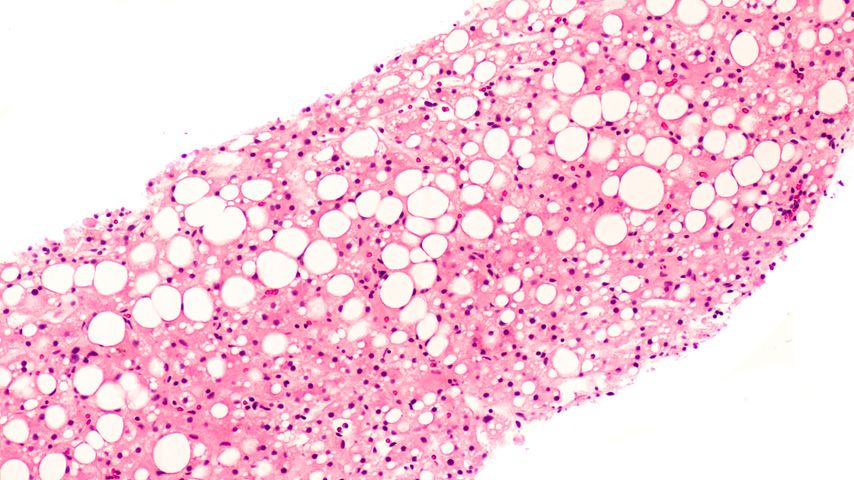

Die MASLD («metabolic dysfunction-associated steatotic liver disease») ist eine Stoffwechselerkrankung, die mit einer Einlagerung von Fett in der Leber einhergeht.1 Die epidemiologischen ...

Viele Menschen mit Adipositas oder Typ-2-Diabetes entwickeln im Verlauf eine mit metabolischer Dysfunktion assoziierte Fettlebererkrankung (MASLD). Die MASLD wird immer noch zu selten ...

Die gemeinsame Leitlinie für das Management der mit metabolischer Dysfunktion assoziierten steatotischen Lebererkrankung (MASLD) der European Association for the Study of the Liver (EASL ...

Die neue europäische Leitlinie zum Management der mit metabolischer Dysfunktion assoziierten steatotischen Lebererkrankung (MASLD) gibt detaillierte Empfehlungen zu Diagnose, Behandlung ...